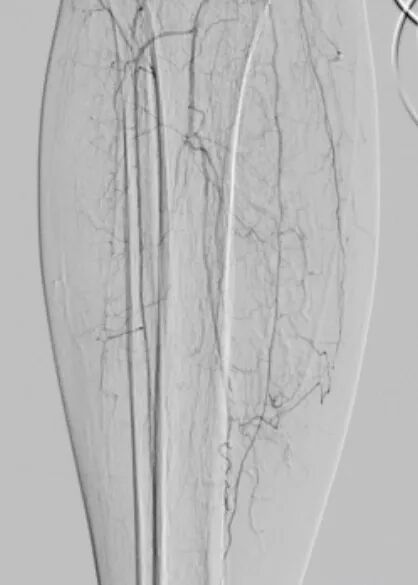

术中,血管外科团队以IVUS为“导航”,在其实时监视下,导丝精准找到血管真腔入口,顺利通过全程闭塞段,成功避免夹层发生,顺利打通患者腿部“生命通道”。针对血管开通后管腔内的严重增生性病变,团队采用准分子激光消融术进行减容处理,通过激光导管冷光源精准气化斑块,进一步恢复了血管正常内径。

8术前IVUS引导.jpg

9术中激光开通.jpg

术前IVUS引导

术中激光开通